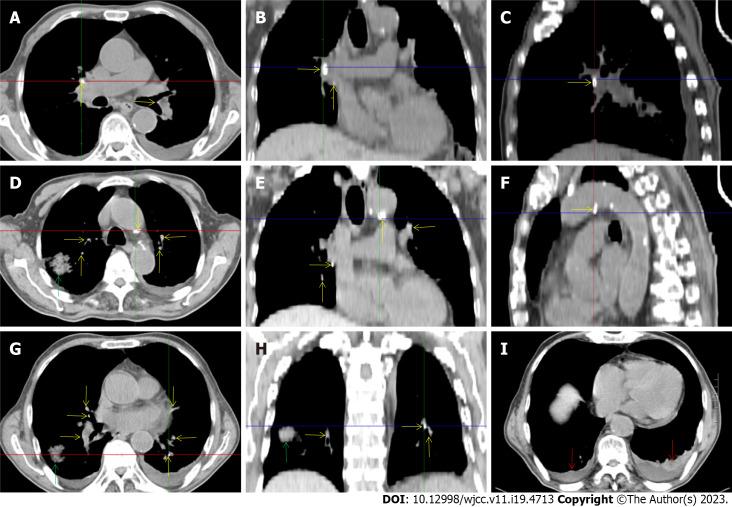

A 72-year-old male patient was definitively diagnosed with MDS with excess blasts-1 (MDS-EB-1) based on an increase in the percentages of myeloblasts and cluster of differentiation (CD)34+ hematopoietic progenitors and the identification of myeloid neoplasm-associated somatic mutations in bone marrow samples. The patient was treated with hypomethylation therapy and was able to maintain a steady disease state for 2 years. In the treatment process, the advanced MDS patient experienced an episode of progressive pancytopenia and bone marrow aplasia. During the aplastic crisis, the bone marrow was infiltrated with sparsely distributed atypical lymphocytes. Surprisingly, the leukemic cells disappeared. Immunological analysis revealed that the atypical lymphocytes expressed a high frequency of CD3, CD5, CD8, CD16, CD56 and CD57, suggesting the activation of autoimmune cytotoxic T-lymphocytes and natural killer (NK)/NKT cells that suppressed both normal and leukemic hematopoiesis. Elevated serum levels of inflammatory cytokines, including interleukin (IL)-6, interferon-gamma (IFN-γ) and tumor necrosis factor-alpha (TNF-α), confirmed the deranged type I immune responses. This morphological and immunological signature led to the diagnosis of severe aplastic anemia secondary to large granule lymphocyte leukemia. Disseminated tuberculosis was suspected upon radiological examinations in the search for an inflammatory niche. Antituberculosis treatment led to reversion of the aplastic crisis, disappearance of the atypical lymphocytes, increased marrow cellularity and 2 mo of hematological remission, providing strong evidence that disseminated tuberculosis was responsible for the development of the aplastic crisis, the regression of leukemic cells and the activation of CD56+ atypical lymphocytes. Reinstitution of hypomethylation therapy in the following 19 mo allowed the patient to maintain a steady disease state. However, the patient transformed the disease phenotype into acute myeloid leukemia and eventually died of disease progression and an overwhelming infectious episode.

一名72岁男性患者,基于骨髓样本中原始粒细胞和分化簇(CD)34+造血祖细胞百分比增加以及髓系肿瘤相关体细胞突变的鉴定,被明确诊断为伴有过多原始细胞-1的骨髓增生异常综合征(MDS-EB-1)。该患者接受了低甲基化治疗,并能够维持稳定的疾病状态2年。在治疗过程中,这位晚期MDS患者经历了一次进行性全血细胞减少和骨髓再生障碍。在再生障碍危象期间,骨髓中浸润有散在分布的非典型淋巴细胞。令人惊讶的是,白血病细胞消失了。免疫分析显示,这些非典型淋巴细胞高表达CD3、CD5、CD8、CD16、CD56和CD57,提示自身免疫性细胞毒性T淋巴细胞和自然杀伤(NK)/自然杀伤T(NKT)细胞激活,抑制了正常和白血病造血。包括白细胞介素(IL)-6、干扰素-γ(IFN-γ)和肿瘤坏死因子-α(TNF-α)在内的血清炎性细胞因子水平升高,证实了紊乱的I型免疫反应。这种形态学和免疫学特征导致诊断为继发于大颗粒淋巴细胞白血病的严重再生障碍性贫血。在寻找炎症病灶的放射学检查中怀疑有播散性结核病。抗结核治疗导致再生障碍危象逆转、非典型淋巴细胞消失、骨髓细胞数量增加以及2个月的血液学缓解,有力地证明了播散性结核病是再生障碍危象发生、白血病细胞消退和CD56+非典型淋巴细胞激活的原因。在接下来的19个月中重新进行低甲基化治疗使患者能够维持稳定的疾病状态。然而,患者疾病表型转变为急性髓系白血病,最终死于疾病进展和严重感染发作。